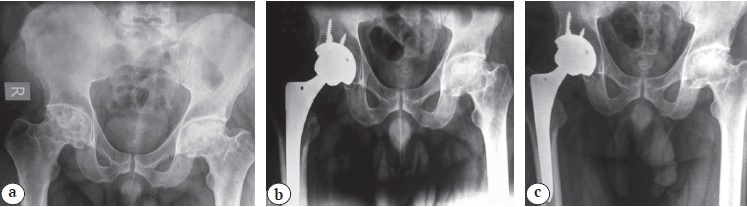

Figure 1. A 36-year-old male patient with bilateral avascular necrosis, right cementless THA (metal-on-polyethylene bearing surface): a — preoperative X-rays; b — X-rays at 6 months post-operatively; c — X-rays at 18 months post-operatively